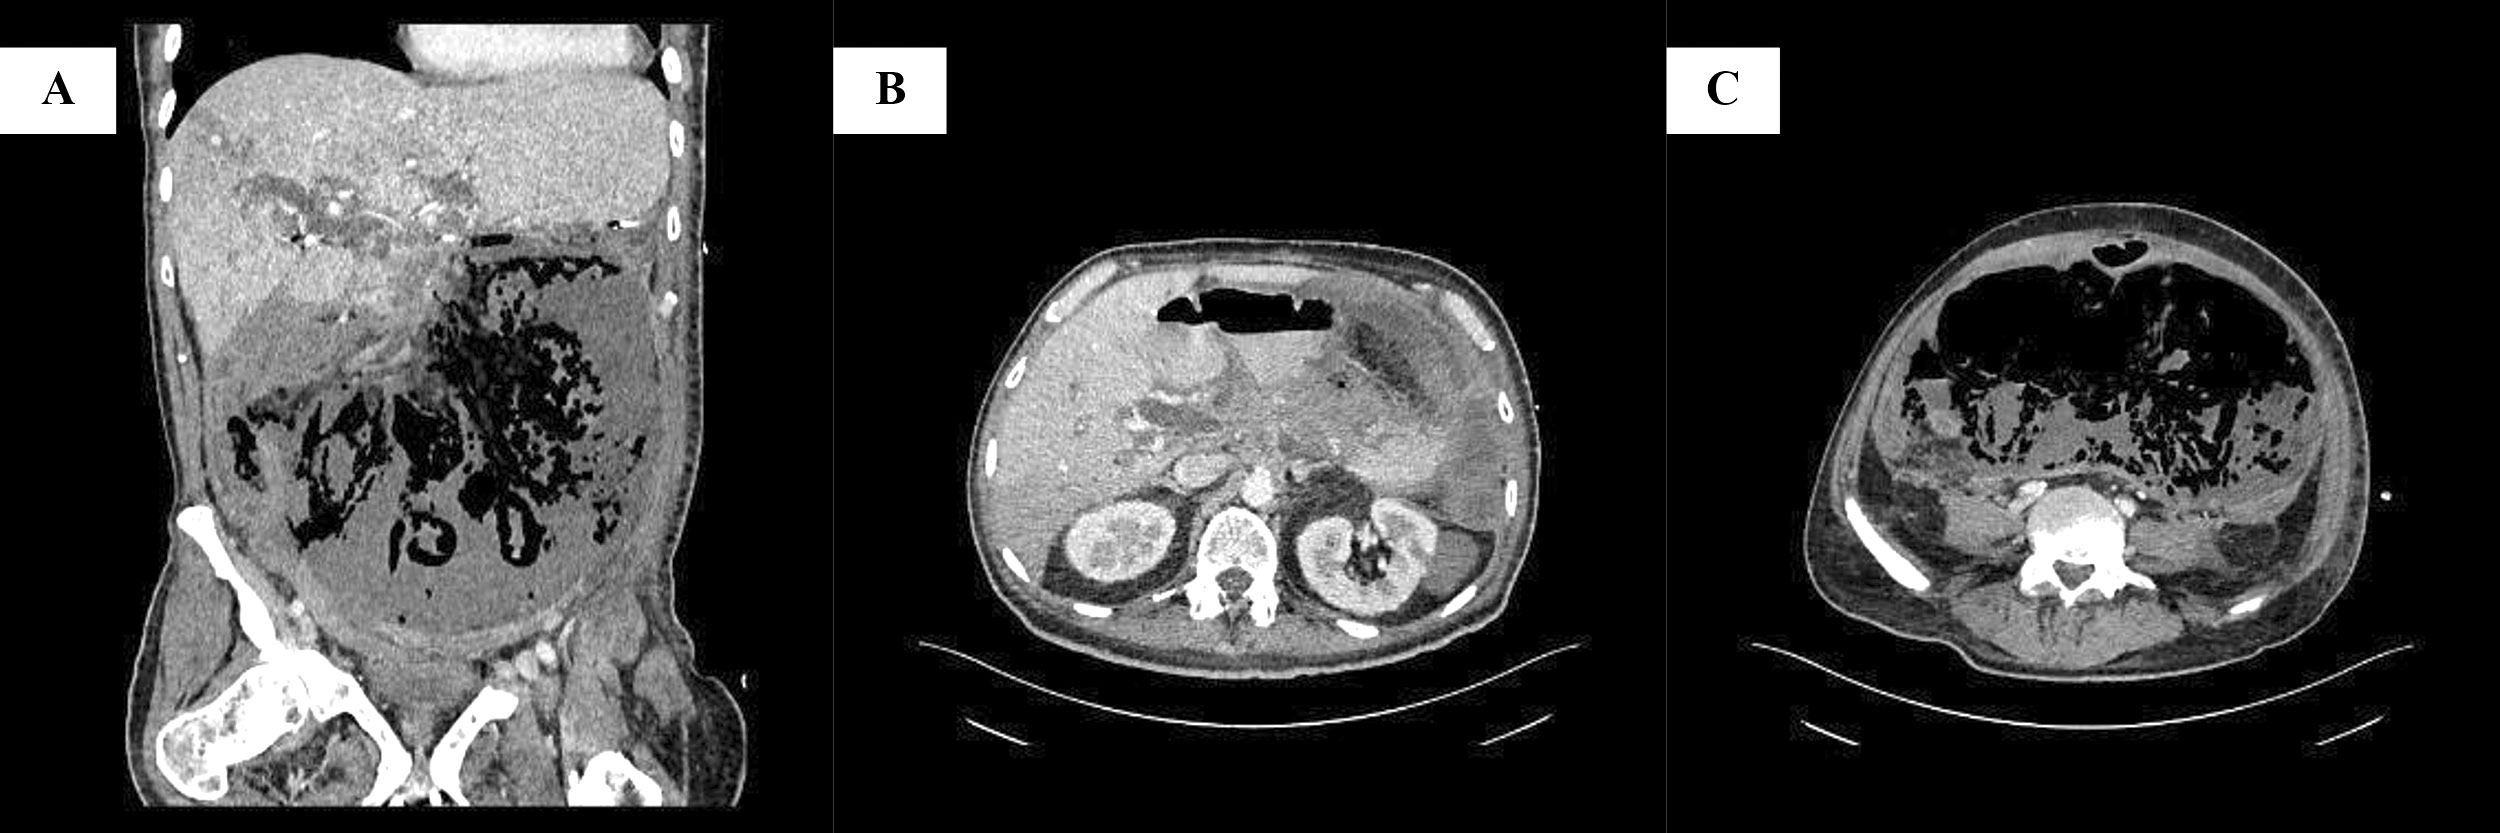

The abdominal clinical examination revealed diffuse tenderness, decreased bowel sounds and loss of dumbness subdiaphragmatically during percussion. These findings suggested bowel perforation as a possible diagnosis. The laboratory tests revealed metabolic acidosis, lactate, elevated d-dimers and leukocytosis. A computed tomography (CT) with intravenous contrast media was carried outwhich demonstrated air subdiaphragmatically and occlusion of the superior mesenteric artery. Other findings were a 5x6 cm lesion in the body of the pancreas with concomitant peritoneal metastasis, suggesting Stage IV pancreatic adenocarcinoma (Figure 1).

Figure 1: Preoperative computed tomography findings. A: Coronal view. Large fluid and air collection inside the peritoneal cavity, surrounded by thickened peritoneum with mild enhancement, due to peritonitis following bowel perforation; diffuse bowel wall thinning with intramural gas bubbles, suggestive of mesenteric ischemia; periportal edema and small peripheral area of hypoattenuation in the liver. B: Transverse view at the level of superior mesenteric artery origin. Extensive hypoattenuating mass located predominantly on the pancreatic body and less on the head, with invasion of the superior mesenteric artery from the level of its origin from the aorta; complete absence of attenuation of the superior mesenteric artery due to occlusion; the lesion extends to the hepatoduodenal ligament and porta hepatis; and dilatation of common bile duct. C: Transverse view at the level of L5. Large collection of fluid and gas in the peritoneal cavity, with thickened peritoneum; and thinning and absence of definition of the bowel wall, due to acute mesenteric ischemia.